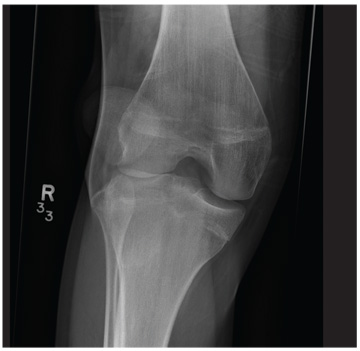

A 20-year-old man presents following a motor vehicle collision in which the car he was driving was broadsided by another vehicle. His air bag deployed, and the patient is now complaining of right-sided chest wall pain and right knee pain. His medical history is unremarkable. In a primary survey, the patient appears stable, with normal vital signs. Inspection of his right knee shows some deformity of the joint, with mild swelling and moderate tenderness. The patient is unable to perform flexion with his right knee. Good distal pulses are present, and sensation is intact. Radiograph of the right knee is obtained. What is your impression?

The radiograph demonstrates lateral dislocation of the patella, with no evidence of an acute fracture of any surrounding bones. The patella was easily reduced in the emergency department, and the patient was placed in a knee immobilizer. Orthopedic consultation was obtained.